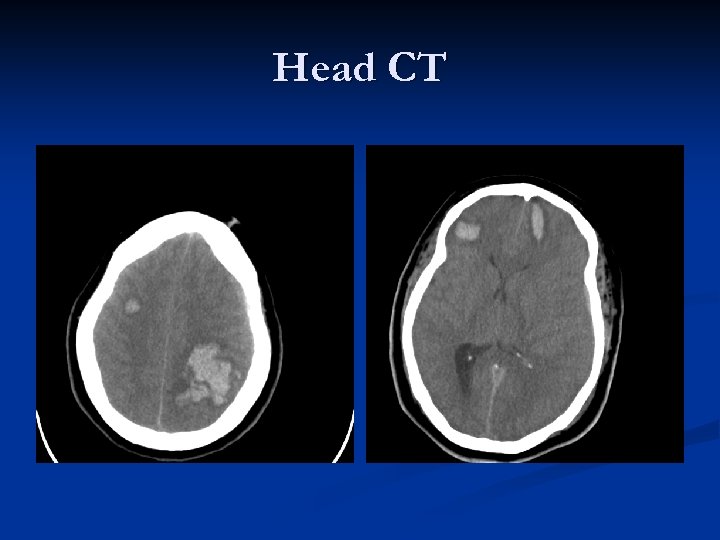

Brain MRI

Case #1 n n n MRI demonstrates parenchymal hemorrhage left frontal lobe that measures 10 x 7 mm. Neurosurgery was consulted; they recommended transfusion of platelets with goal platelet count over 100, 000. Neutropenic fevers were treated with cefepime and supportive care. Follow-up head CT two weeks later showed no increase in the size of hemorrhage. The patient was discharged home once neutropenic fevers resolved.